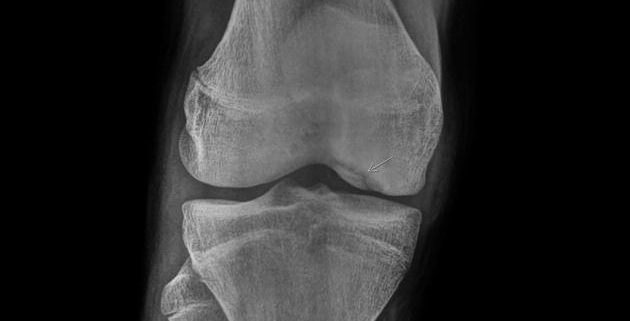

OCD is typically diagnosed through a combination of a physical examination, medical history, and imaging tests. The doctor may check for tenderness, swelling, and range of motion. Imaging tests such as X-rays, MRI, or CT scan provide detailed images of the knee and can help identify any damage or abnormality.